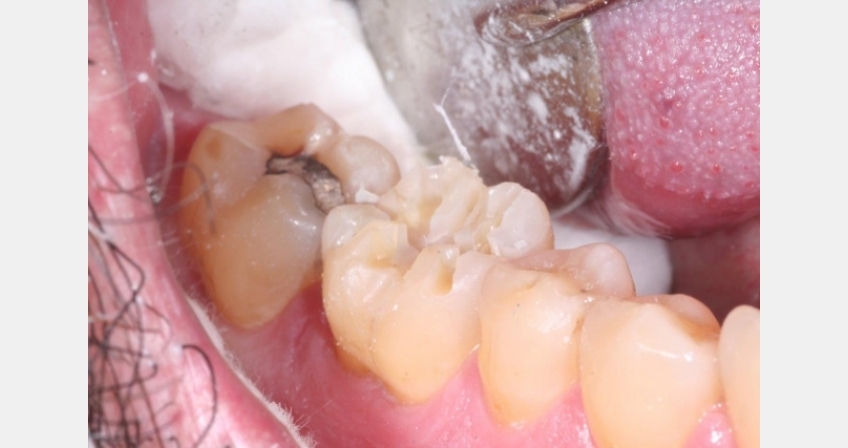

- Remove old restorative material and decay to verify restorability in its current state and need for possible root canal therapy and/or crown lengthening. I also determine if a crown restoration is going to be the most conservative and longest lasting or would the tooth and patient be better served doing an inlay or onlay restoration?

- Isolate the tooth for proper bonding and adhesive protocol to place the build-up material of choice (personally, I like light-cured resin and/or dual-cured resin in areas where light penetration may be challenging. Ensure that your build-up material and bonding agent are compatible. Don’t overbuild the tooth, as this wastes material and can affect the next step’s simplicity.

- Now we are ready for the crown preparation (if a tooth will definitely need a crown, e.g. root canal posterior molar with large filling, then I will start with this step first). First thing first: I start with depth cuts on the occlusal table with a known length bur (there are specific depth-cutting burs as well) that is for the needed reduction of the restoration of choice. I take this bur down the central groove, across the cusps, and out the grooves to depth. Now, there is no confusion of how much to remove.

- I will then place a small-diameter bur (KS0 is my bur of choice) to remove the pieces of tooth sticking up between the depth cuts. I essentially place the bur in the groove and either push or pull, which cuts or “amputates” that segment of the tooth off rather quickly and efficiently.